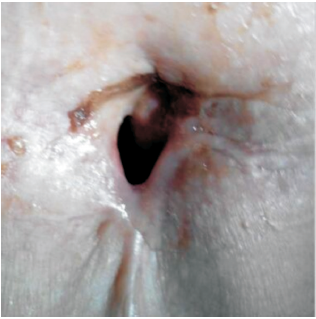

高惠冰:2014年3月患者出现吞咽困难、左耳刺痛、喉部异物感。来院查体: PS评分1分, 颈部见气管造瘘口, 造瘘口右上方可触及肿物。大小约4 cm× 3 cm, 质韧, 活动度差, 无压痛。

2014-03-26喉增强MRI:喉部术后改变, 喉腔内见巨大软组织肿块影, 大小约41 mm× 29 mm, 信号均匀, 边界不清, 增强后病灶明显均匀性强化, 喉腔变窄、消失, 病灶向上累及会厌皱襞, 下缘达甲状腺水平, 见图6和图7, 无病生存期14个月。

诊断:喉鳞状细胞癌术后造瘘口复发rT4aN0M0 Ⅳ A期。